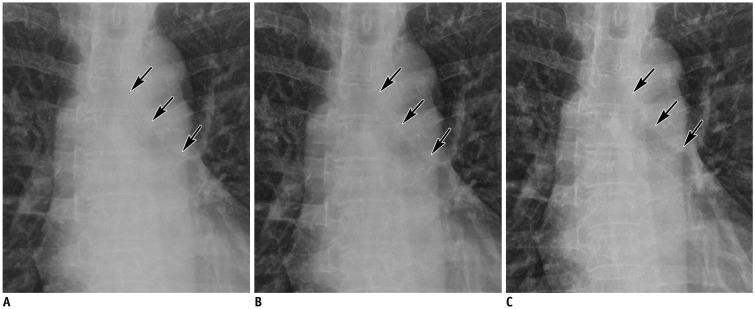

Each of the 38 patients underwent bedside chest radiography with and without a grid. A grid-like image was generated from a non-grid image using SimGrid software (Samsung Electronics Co. Ltd.) employing deep-learning-based scatter correction technology. Two readers recorded the preference for 10 anatomic landmarks and the overall appearance on a five-point scale for a pair of non-grid and grid-like images, and a pair of grid-like and grid images, respectively, which were randomly presented. The dose area product (DAP) was also recorded. Wilcoxon's rank sum test was used to assess the significance of preference.

Both readers preferred grid-like images to non-grid images significantly ( < 0.001); with a significant difference in terms of the preference for grid images to grid-like images ( = 0.317, 0.034, respectively). In terms of anatomic landmarks, both readers preferred grid-like images to non-grid images ( < 0.05). No significant differences existed between grid-like and grid images except for the preference for grid images in proximal airways by two readers, and in retrocardiac lung and thoracic spine by one reader. The median DAP were 1.48 (range, 1.37-2.17) dGycm in grid images and 1.22 (range, 1.11-1.78) dGycm in grid-like images with a significant difference ( < 0.001).

The SimGrid software significantly improved the image quality of non-grid images to a level comparable to that of grid images with a relatively lower level of radiation exposure.